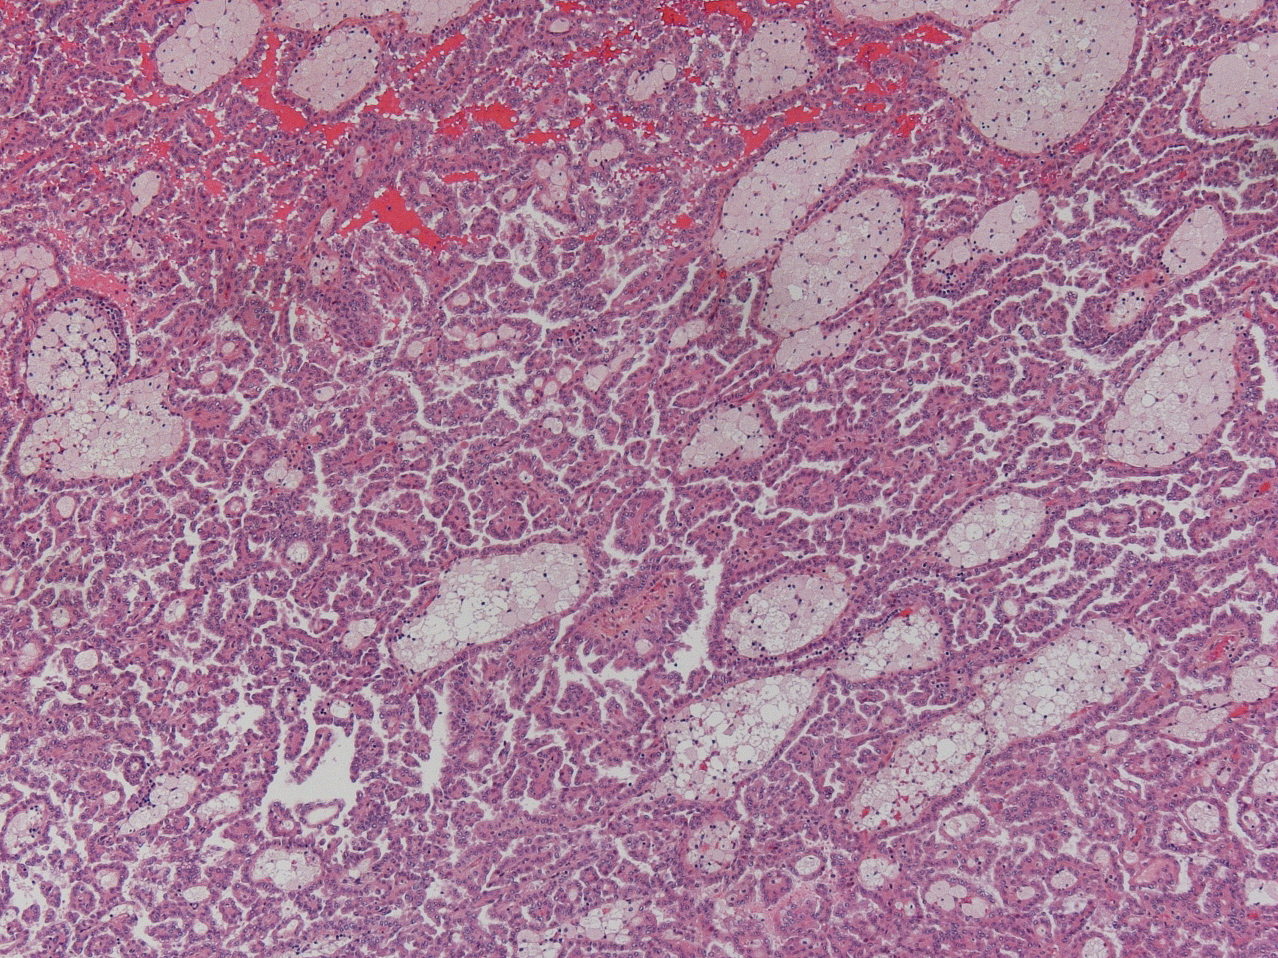

Renal tumor grading

Case ID: 928